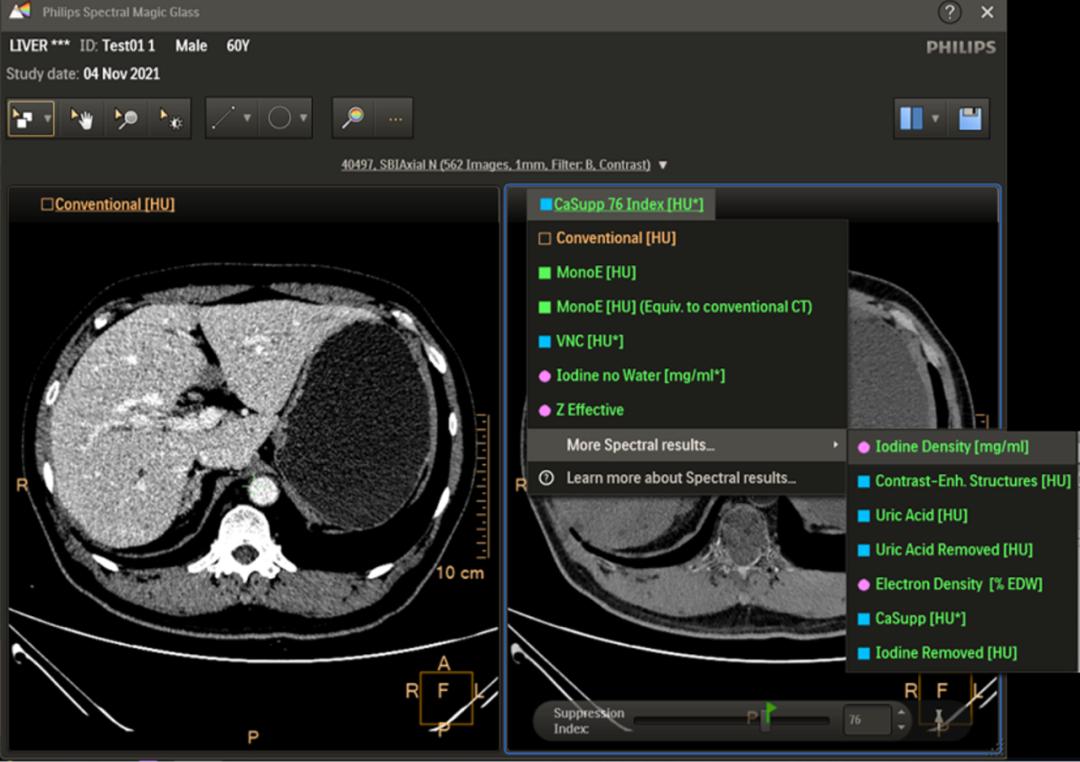

独有的云魔镜技术,加速光谱诊断流程

云魔镜这一独有的轻量级光谱多参数图像可视化方案,可以让医生在阅片和签报告时随时随地随心对疑难病种的光谱多参数进行诊断。同时,针对常规CT不易看清、易漏诊的病灶,调用云魔镜可实现光谱多参数的可视化诊断,并对随访病例进行定量分析。

光谱云魔镜技术